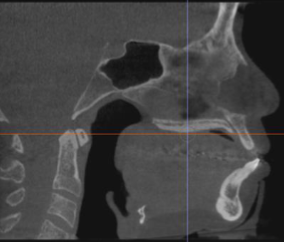

sagittal

what plane is this